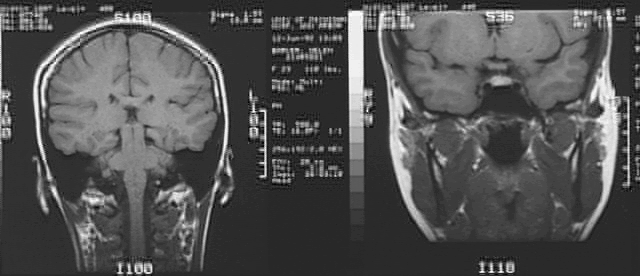

Radiology Images

Head & Neck: Head MRI 2 of 3: